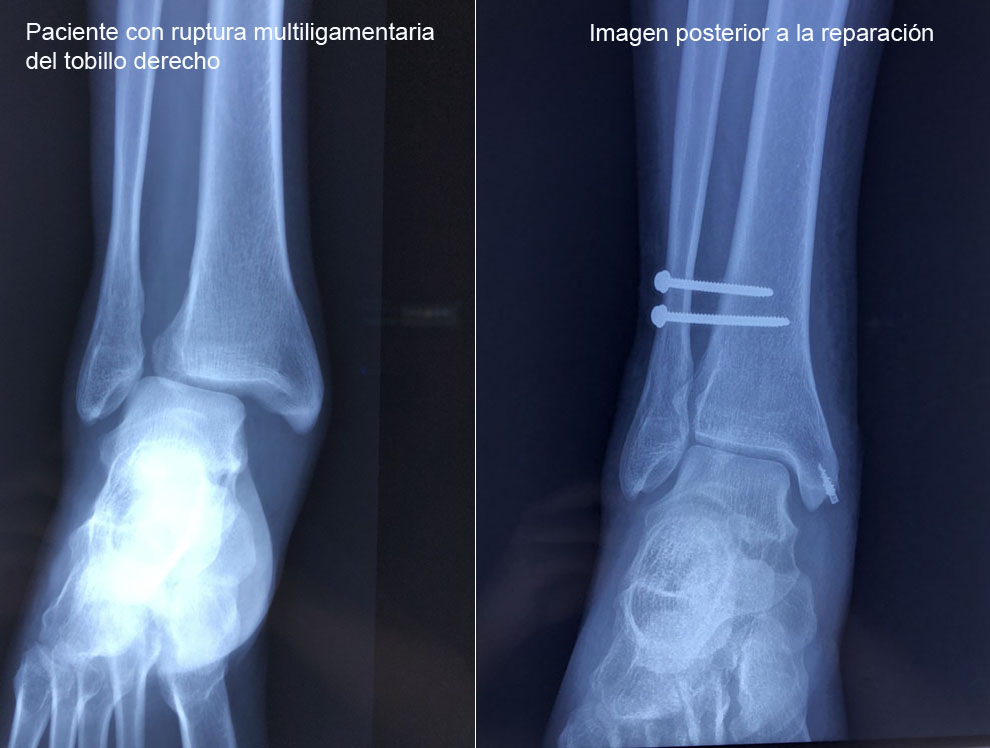

Los esguinces son lesiones ligamentarias que pueden variar en diversos grados de severidad, los cuales pueden ser desde una simple distensión de las fibras hasta una rotura total de las mismas. Por lo que es indispensable una adecuada valoración y un tratamiento oportuno para evitar las complicaciones.

El ligamento deltoideo es el principal estabilizador medial del tobillo, evita que el tobillo se vaya en eversión. El ligamento está formado por dos capas. Su ruptura condiciona inestabilidad medial del tobillo.